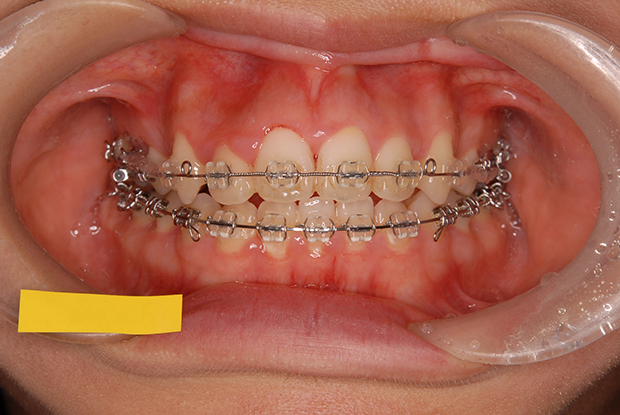

【叢生】抜歯 表側マルチブラケット装置

| 主訴 |

ガタガタ、上の歯が裏側に入っている |

||

|---|---|---|---|

| 診断名 |

左側側切歯crossbiteを伴うAngle I級上下顎前突 |

||

| 年齢 | 21歳 | 性別 | 女性 |

| 治療に用 いた装置 |

唇側マルチブラケット装置 (メタルワイヤー) | 抜歯部位 | 上下顎両側第一小臼歯 |

| 治療期間 ・回数 |

2年6か月・30回 | 治療費 概算 |

約75万円 (調整料を含む) |

| 治療内容 詳細 |

表側のマルチブラケット装置で治療した典型的な抜歯症例です。抜歯したスペースを利用して前歯を後退させ、ガタガタを解いています。 |

||

| リスク・ 副作用 |

装置による違和感。疼痛など |

||